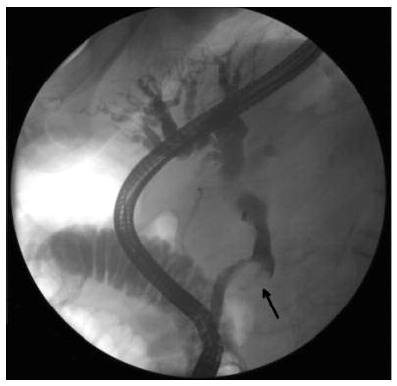

The physical examination was unremarkable except for icteric sclera. The patient’s laboratory values were as follows: total bilirubin level, 220.642 µmol/L (normal range, 5.0-21.0 µmol/L); alkaline phosphatase, 19.305 µkat/L (normal range, 0.5-2.0 µkat/L); aspartate aminotransferase, 5.318 µkat/L (normal range, 0.17-0.51 µkat/L); alanine aminotransferase, 6.296 µkat/L (normal range, 0.17-0.68 µkat/L); gamma-glutamyltransferase, 4.334 µkat/L (normal range, 0.03-0.51 µkat/L); and alpha fetoprotein, 36.8 µg/mL (normal range, 0-20 µg/mL). The results of a complete blood count were within normal limits. Computed tomography scanning revealed a 5.2 × 5.7 cm mass abutting the pancreas head (Figure 3). Endoscopic retrograde cholangiopancreatography showed an obstruction by the compressing mass at the level of the midportion of the common bile duct. This endoscopic retrograde cholangiopancreatography picture may have represented intraluminal invasion of the mass with no effect on the pancreatic duct (Figures 1 and 2). Fine-needle aspiration biopsy of the mass revealed malignant cells.